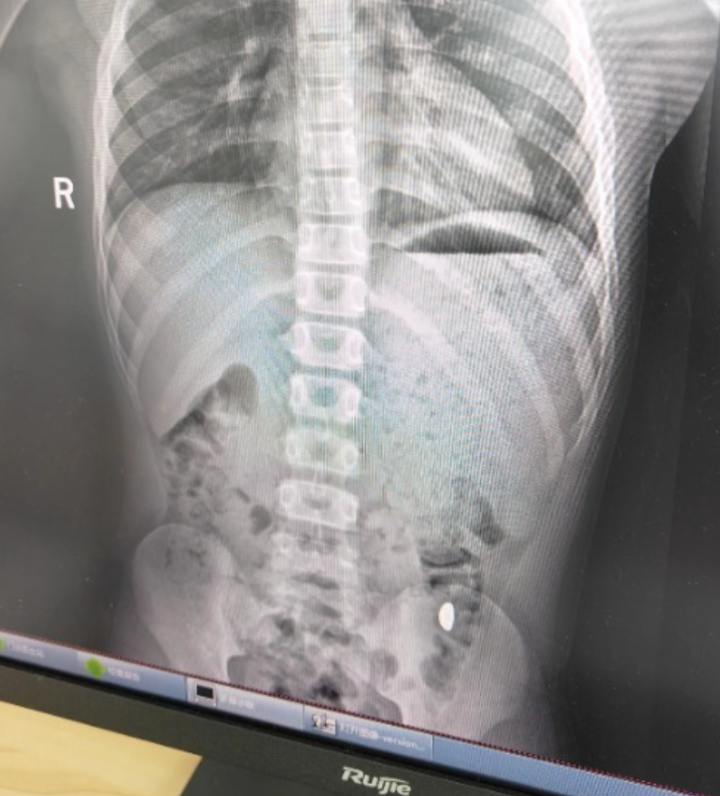

昆山市第五人民医院门诊病历单显示,患儿5天前误吞约10克黄金,其间解两次大便未发现,目前无腹痛、呕吐等症状,诊断结果显示胃内有异物。

右下加亮点为金豆。

X光片显示金豆已运行到降结肠了,非在胃内。医生说胃内有异物是错误的。